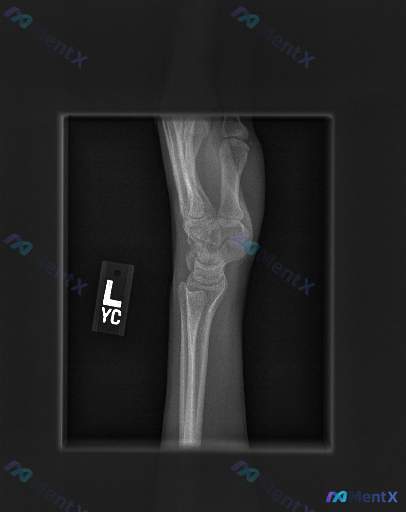

整理到一份左侧腕部侧位X光片的读片资料,先跟大家同步一下影像层面的发现:

✅ 各骨性结构(桡骨远端、尺骨茎突及全部腕骨)轮廓完整,未见明确骨折线、皮质中断或台阶征

✅ 桡骨-月骨-头状骨序列共轴关系基本维持,腕骨间排列整齐,无脱位或半脱位征象

✅ 关节间隙清晰,未见明显狭窄或异常增宽

✅ 骨小梁结构清晰,未见骨质破坏、囊变或硬化

✅ 软组织轮廓清晰,未见明显肿胀或脂肪垫移位